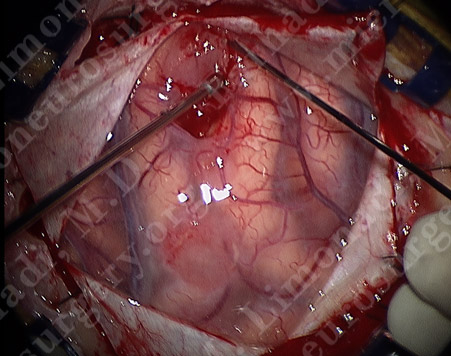

One of the tumors being removed.

Utilizing computer navigation, a small craniotomy was performed precisely over the tumor and both tumors were removed using this small opening.